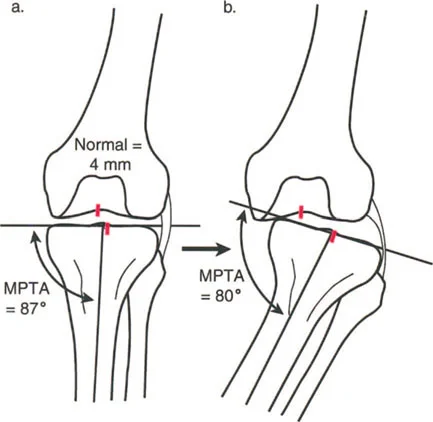

تقوس وفحج الجزء البعيد من عظم الساق

تتحدد درجة الشذوذ في المشي في تشوهات المستوى الأمامي للج